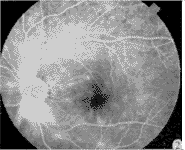

图1 典型病例治疗前眼底普通像   图2 治疗前荧光素眼底血管造影像

图3治疗后黄斑水肿消失